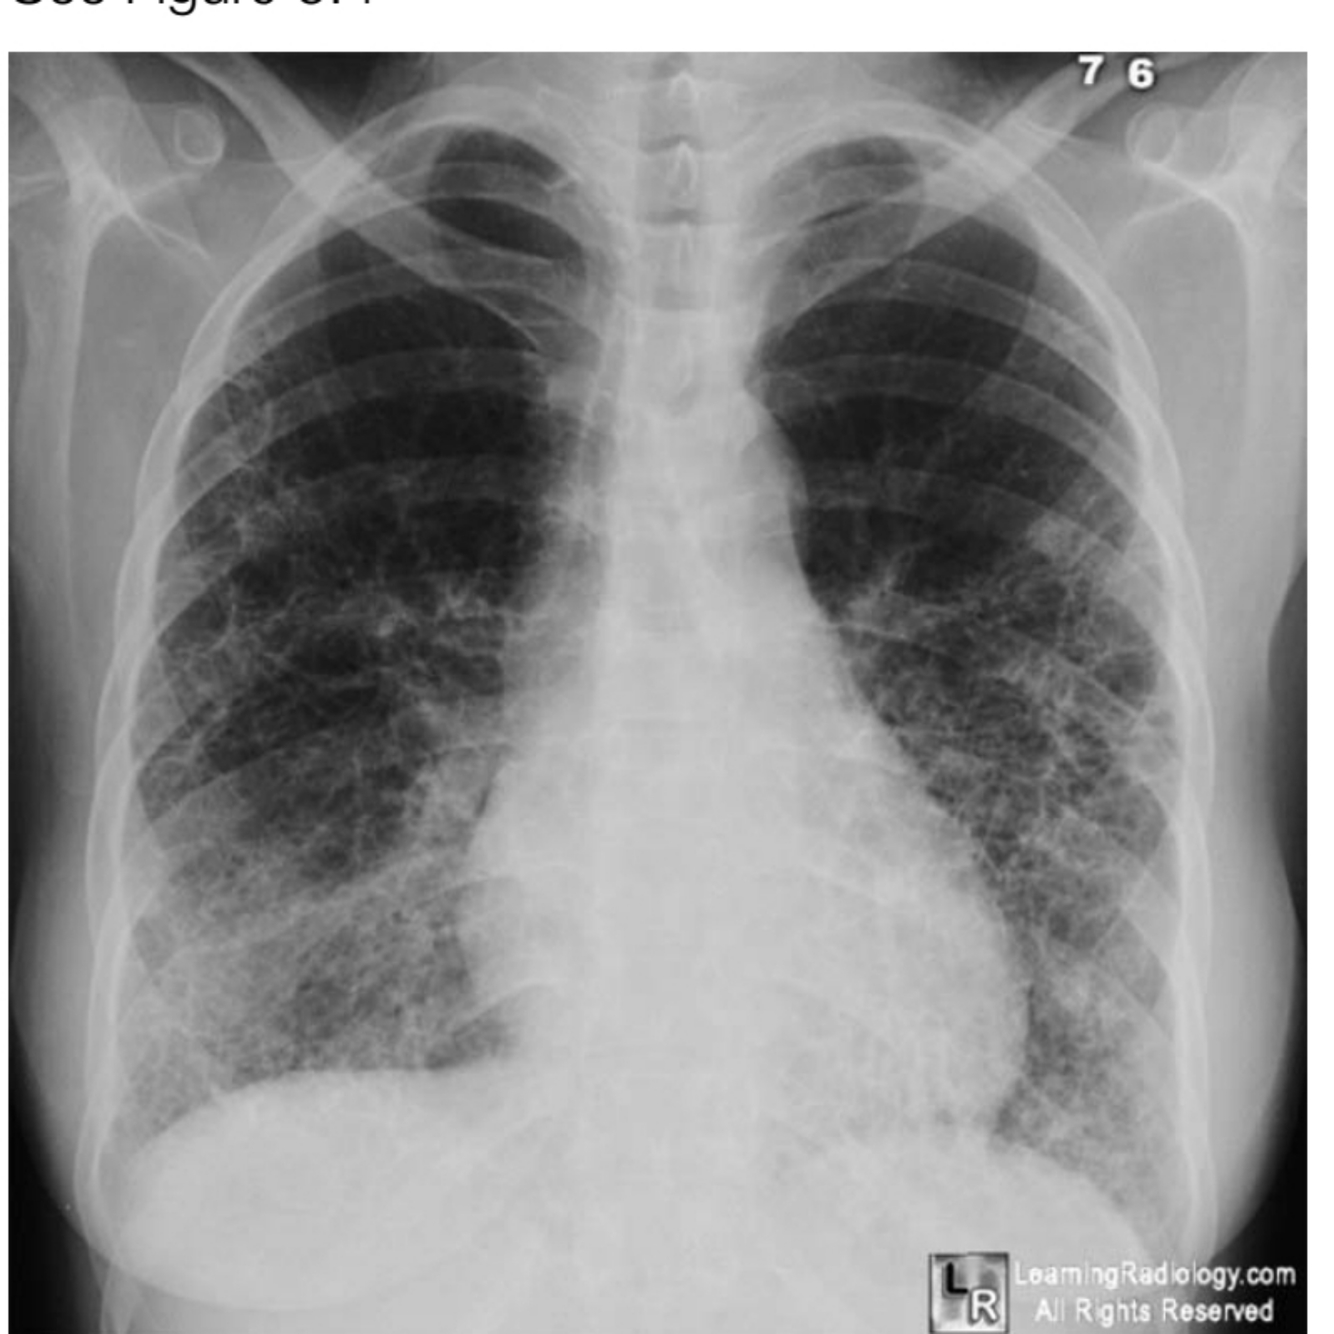

arthritis, is booked for a total knee replacement. Can you tell me the positive findings on her chest X-ray.

A

Bilateral airspace disease with:

• Extensive reticular change throughout both lungs

• Reduced volume

• Honeycomb pattern

• Shaggy heart border

Diagnosis: Pulmonary fibrosis. This can be because of the disease

progression or as a side effect of drugs for rheumatoid disease.